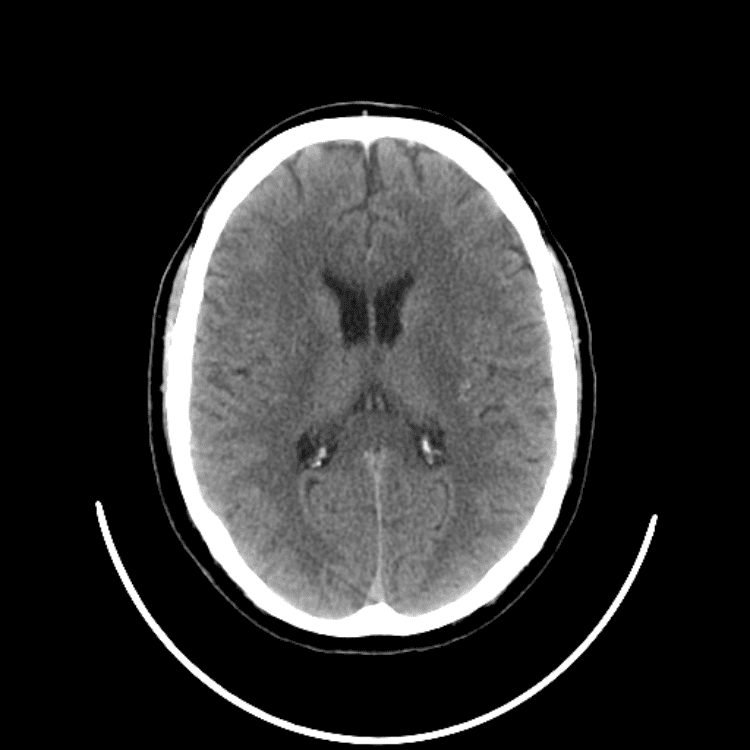

Nontraumatic Brain

Classic